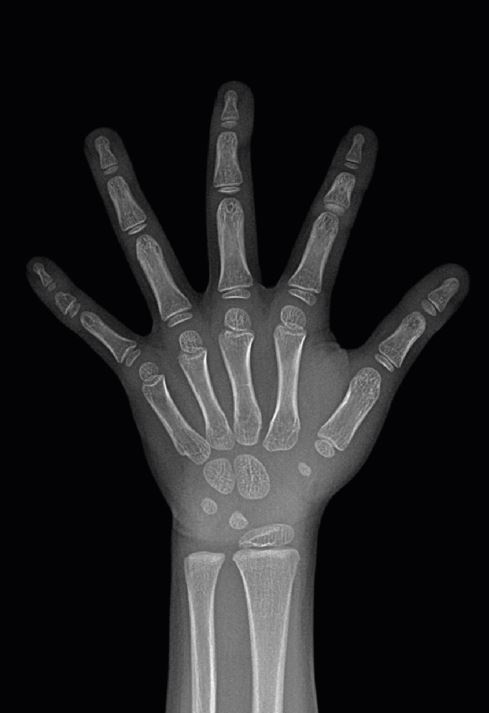

![연세굿데이치과] 성장판 검사가 중요한 이유 관련 이미지 2](https://pub-9f2bb3498faf4d1d8714b41df24753e3.r2.dev/content/clinics/archive/5hurea2jnb/naver_blog/eunkyo3370/assets/by_hash/e95672fd1edbaef49d104e178fe66272de0de7392d580faed610c06bb14c9ae3.jpg)

(좌)19세 성장판, (우)5세 성장판